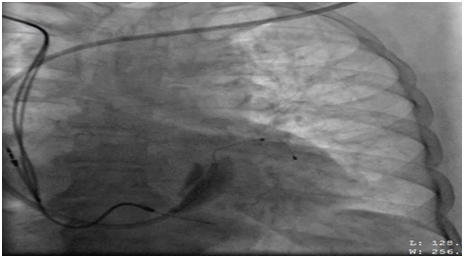

62 years old lady presented to the electrophysiology clinic with a history of shortness of breath, orthopnea, paroxysmal nocturnal dyspnea and lower limb swelling have started 3 weeks back. She denied any chest pain or syncope. She is known as HTN, IHD (S/P PCI to LAD 10 years ago), and History of Complete heart block (S/P DDDR pacemaker 6 years back). Previous LV function was normal (EF >55%, No significant valvular disease). On examination: She was conscious, oriented and vitally stable BP: 110/70 HR 70B/M, regular, RR: 22, Pso2: 96% on room air, T : 36.5, Congested neck vein observed, Chest: bilateral fine end in inspiratory basal crackles CVS: Normal S1, S2, no add sound or murmur Abdomen: Lax, soft, no masses Lower limb: Bilateral pitting edema ECG: well functioning paced rhythm; patient was diagnosed as new acute decompensate heart failure which was confirmed by ECHO showed: EF <35 %, with an impressive ventricular dyssynchrony, no significant valvular lesion, The patient was admitted in CCU as a case of ADHF (as a complication of RV pacing), was started on Ant failure treatment and the decision was taken to upgrade the DDDR TO CRTP. Then, Patient was driven in to Catha Lab. The procedure was initially attempted on the right, with successful cannulation of the right subclavian vein but unable to advance the guide wire to the superior vena cava (SVC), Venogram through the right anti-cubital vein showed a short occlusion of the right subclavian vein (Figure 1). The procedure was abandoned and LV lead implantation was performed on the left (Figure 2). Mild dissection of the coronary sinus occurred (Figure 3). Then sealed spontaneously and the LV lead was secured deeply in the posterolateral CS branch, a pair of long forceps were used for blunt dissection to create a subcutaneous tract from the right to the left. The proximal end of the LV lead was grasped with the forceps and tunneled above the sternum to rejoin the pocket (Figure 4). Then programming was done with good homeostasis.